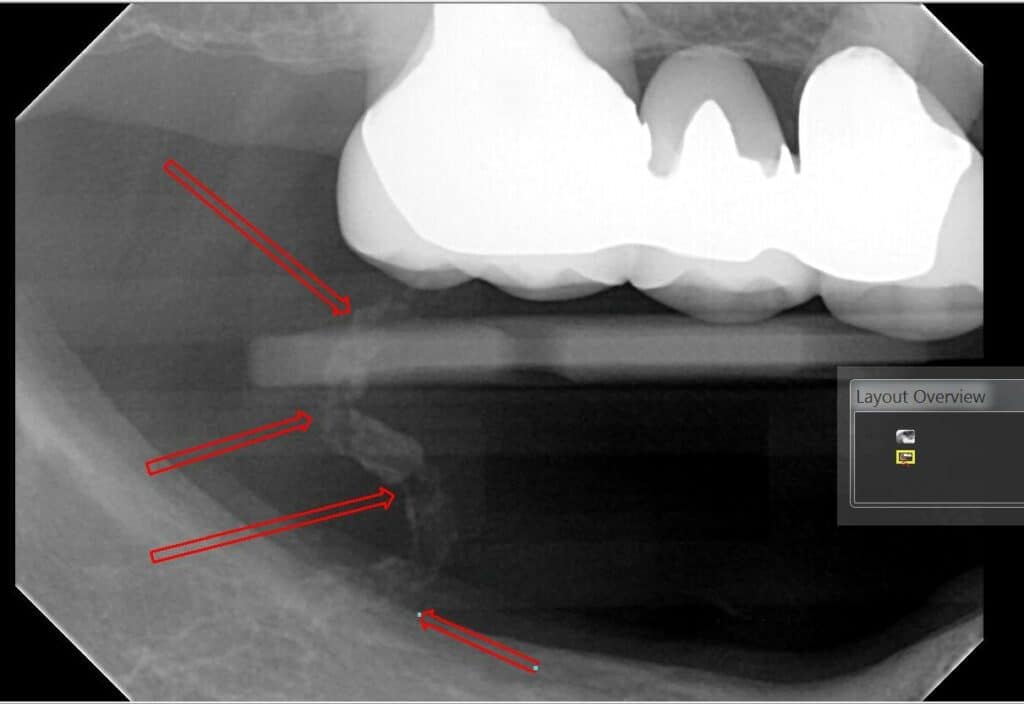

Cemental Tear

A cemental tear is a special type of surface root fracture that may cause periodontal and/or periapical bone destruction. In a cemental tear, a layer of cementum is separated from the underlying root dentin as a result of excessive occlusal forces or trauma to the jaws. This sheared-off fragment remains within the periodontal ligament and acts as a constant irritant. On radiographs, this appears as a linear radiopacity that parallels the adjacent root surface. While usually completely separate, some fragments may remain attached to the root surface.

Cemental tears can present as part of apical periodontitis but can also occur independently with a vital pulp. Soft tissue swelling, localized periodontal pocket, periodontal/periapical bone loss are noted clinical characteristics of cemental tears.

Treatment options include nonsurgical scaling and root planing, surgical debridement with periodontal/apical surgery, surgical debridement combined with GTR and bone grafting, and extraction.